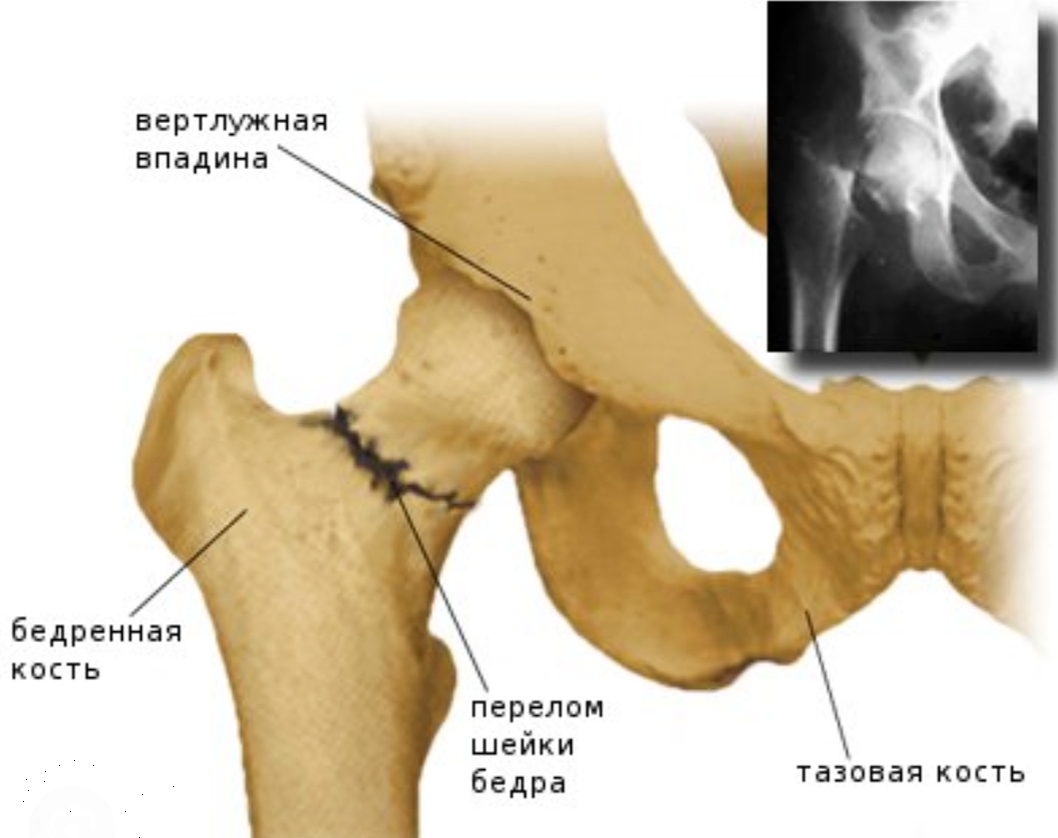

Перелом шейки бедра

Перелом шейки бедра, или чрезвертельный перелом шейки бедренной кости – довольно распространённая и опасная патология, которая, в большинстве своём, встречается у людей пожилого возраста. Так же стоит отметить, что данной травме больше подвержены женщины (1 случай у мужчин на 2-3 случая у женщин). Хотя, конечно, случится это может в любом возрасте.

Сама шейка бедра – это ответвление от бедренной кости в верхней её части, имеющее головку, которая входит в тазобедренный сустав. Через тазобедренный сустав нижние конечности соединены с тазом. Данные суставы обеспечивают не только целостность скелета, но и подвижность ног в пределах нормы работы этих суставов.